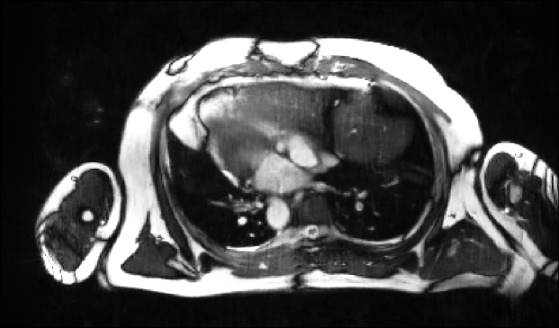

Figure 3 shows an example of cine images reconstructed with the methods reported. We see that our proposed approach accurately removes undersampling artifacts and clearly outperforms baseline comparison methods. Table 1 lists the metrics on the (cropped) CMRxRecon validation dataset as reported by the public leaderboard.

| Coilwise U-Net | E2E-VarNet | Proposed | GT / RSS |